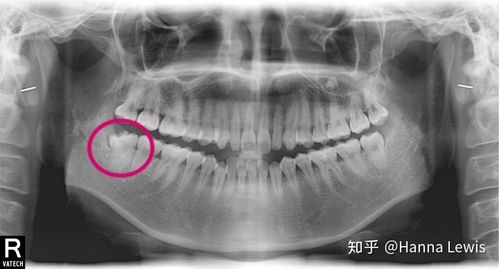

智齿的x光片,智齿x光片图片

询问各位朋友,本人24岁,现在有智齿x光片,智齿位置我有标记红色标点.